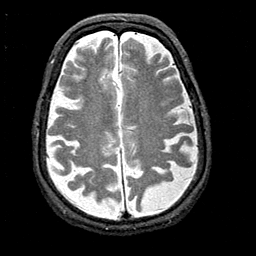

Alzheimer's disease MR T2-weighted -- Slice #33

Tour 2: Next/Previous/Start: Find the central sulcus. To get properly oriented, view the MPEG movie ("cine" button, next to the sagittal image) of the entire dataset, and find the central sulcus by first locating the marginal sulcus in the medial parietal lobe. From the marginal sulcus, the central is usually the first encountered when moving anteriorly. Compare this with the functional image at the same level (use the buttons at right, or choose the SPECT-Tc tickmark on the timeline). Note that both pre- and post- central gyri, where the primary sensori-motor cortices are located, are relatively hyperperfused. In general, Alzheimer's disease is associated with reduced brain function, especially in non-primary regions. The association cortex of the parietal lobes is often severely affected, as illustrated in this case.

[Home][Help][Clinical][Tour 1][Tour 2] Slice 33